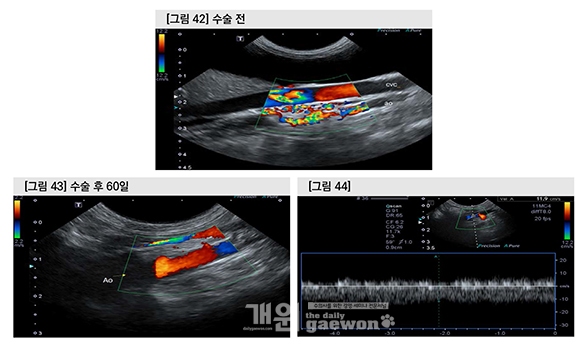

Portal blood flow velocity는 11.9 cm/sec로서 참고범위를 회복 하였으며, 최초 내원 시에 Aortal의 ventral aspect에서 관찰되었던 vessel plexus는 CF doppler 상에 관찰되지 않았다.

Acquired PSS가 관찰되지 않고 normal flow가 완전히 회복되어 약물 및 처방사료는 종료하였다.